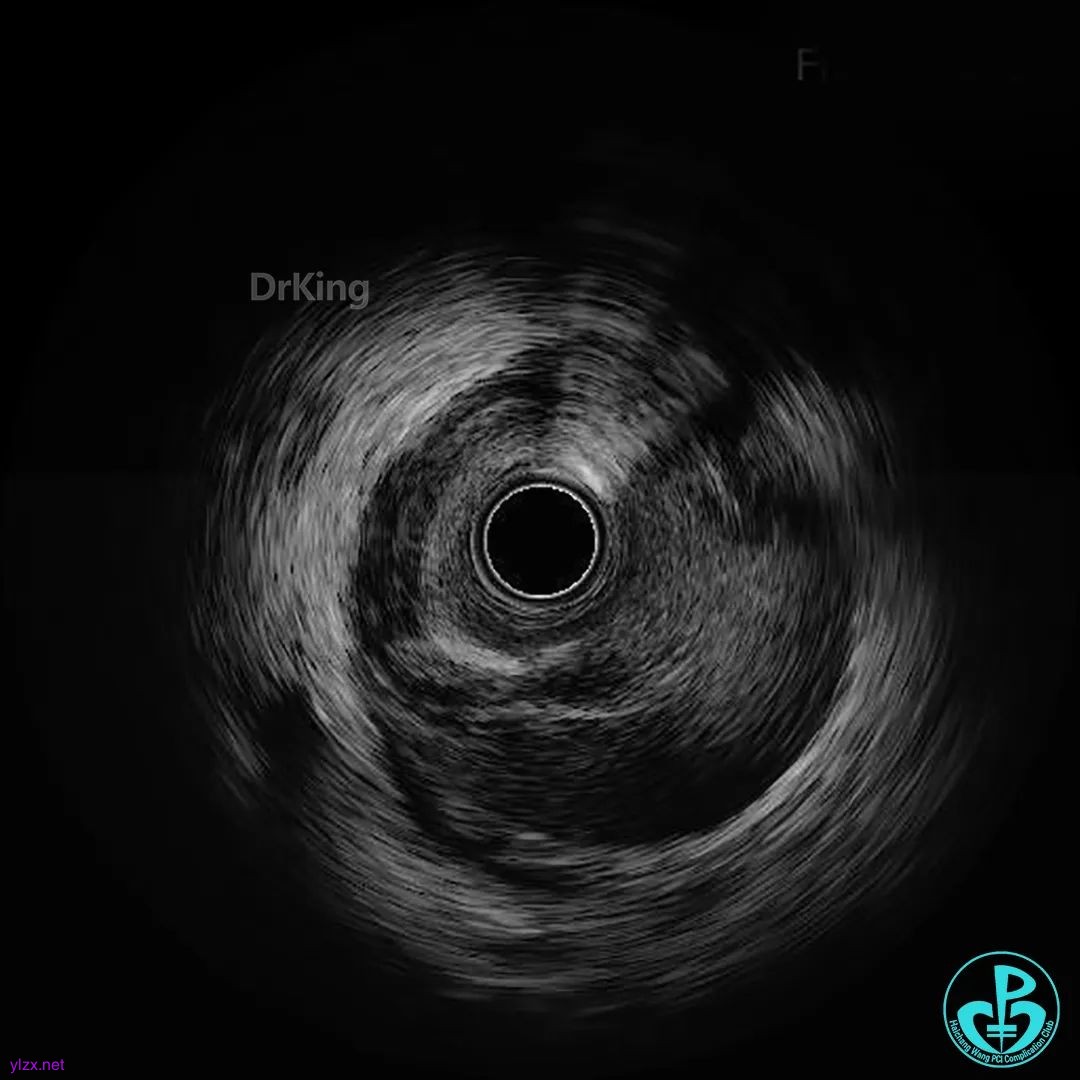

超声证实PL延伸至近端血肿,近端可见夹层破口。

超声证实支架膨胀及贴壁良好,血肿消失,症状缓解。好惊险!